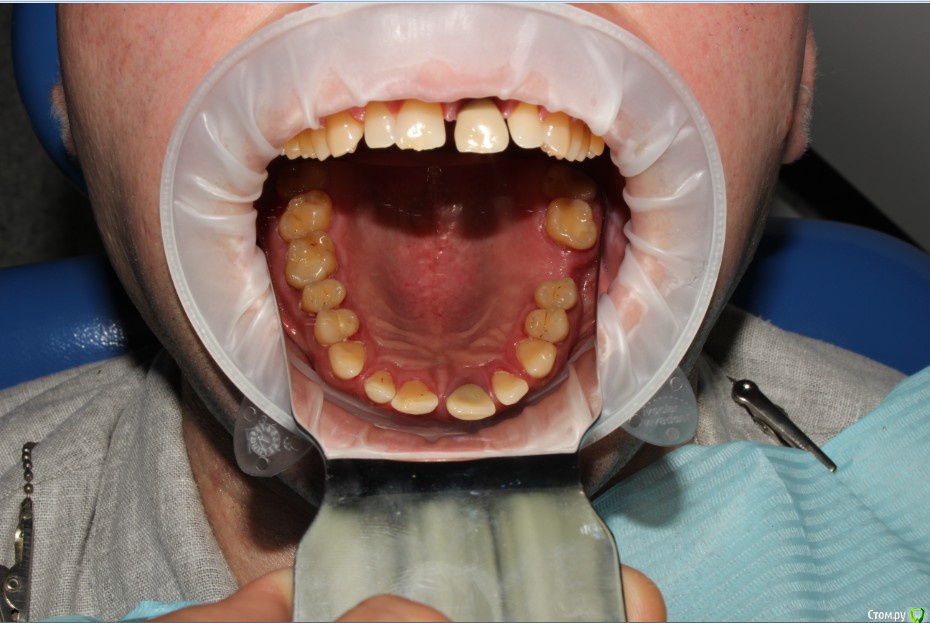

Рустам Опубликовано 20 июля, 2015 Поделиться Опубликовано 20 июля, 2015 Здравствуйте коллеги! Подскажите по клиническому случаю пожалуйста. Обратился пациент в клинику с подвижной коронкой на зубе 2.1, на рентгене диагностирован перелом корня, планируем удаление с одномоментной имплантацией и желательно с немедленной нагрузкой. Система имплантатов "Osstem", на этой системе я ранее не протезировал (работал с "Mis" и "Super Line") и вообще ранее немедленно не нагружал имплантаты. Хирург назначил удаление и иплантацию на 23.07, я смогу принять пациента только 24.07 утром, необходимо заказать временный абатмент, подскажите какой именно из каталога нужно заказать?Имплантолог заказал два имплантата Osstem TSIII SA диаметром 4,0 и 4,5.Я планирую делать временную прямым способом по ключу снятому со старой коронки во рту. Может лучше через оттиск заказать лабораторную временную?P.S. пациента эстетически все устраивало, ортодонтию не хочет. Ссылка на комментарий